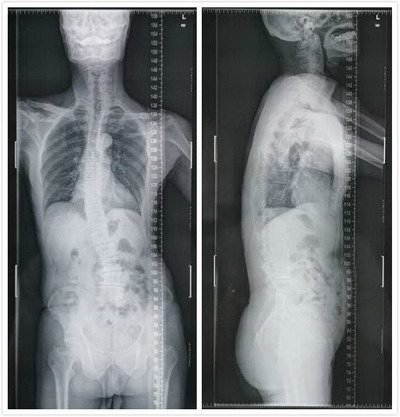

从李大爷就诊时的X光片可见,他的脊柱出现了明显的歪斜,腰椎部分更是明显地倒向一边,看起来就像是意大利著名的景点“比萨斜塔”。

患者术前X光片

患者主诉症状已有十几年,刚开始仅是左侧腿脚活动受限,但由于经济方面的原因迟迟不肯就医,只勉强拖着脚走路,直到最近发现右边腿脚也开始出问题了才来就诊。经检查,发现他的退变性腰椎侧凸已经合并了明显的椎管狭窄,神经受压。拖延使患者的病情明显加重,术前患者已几乎失去行走能力,脊柱矢状面、冠状面都处于失衡状态,这时患者手术的难度也因此增加。